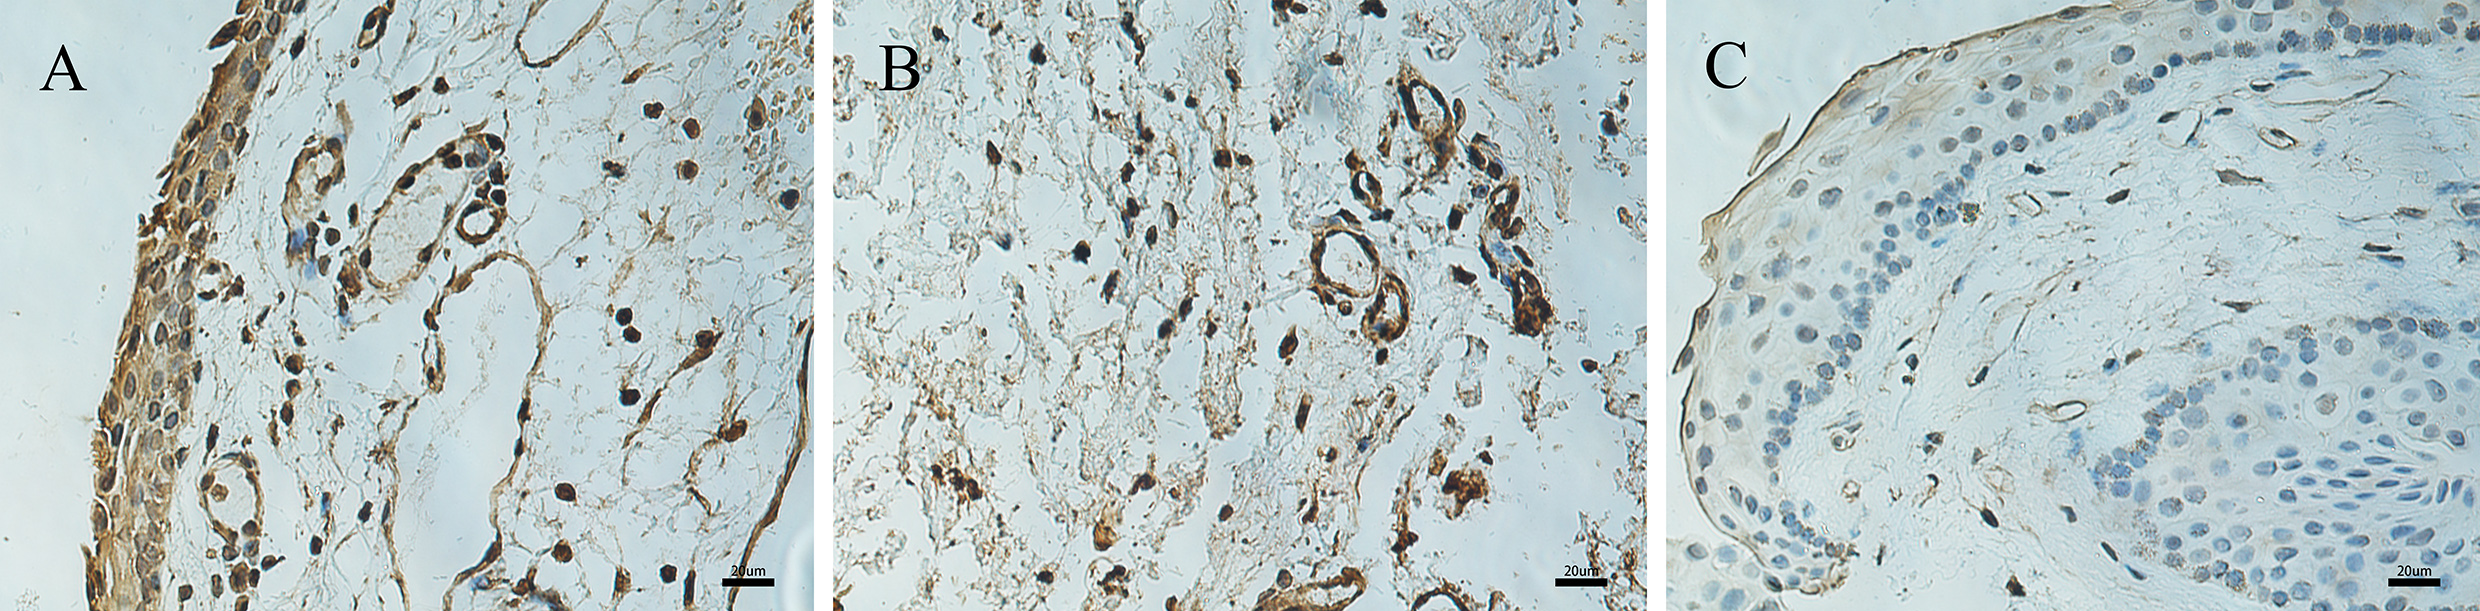

Figure 2. Immunohistochemical expression of HIF-1α in pterygium and normal conjunctiva. Immunohistochemical expression of HIF-1α in

pterygium (A–B) and normal conjunctiva (C). A: Strong nuclear and cytoplasmic immunoreactivity in all epithelial layers of the pterygium sample. B: A large number of vascular endothelial cells in the stromal layer show brown positive staining. C: Weak cytoplasmic immunoreactivity is detected in the control conjunctival sample (400X, bar = 20 μm).